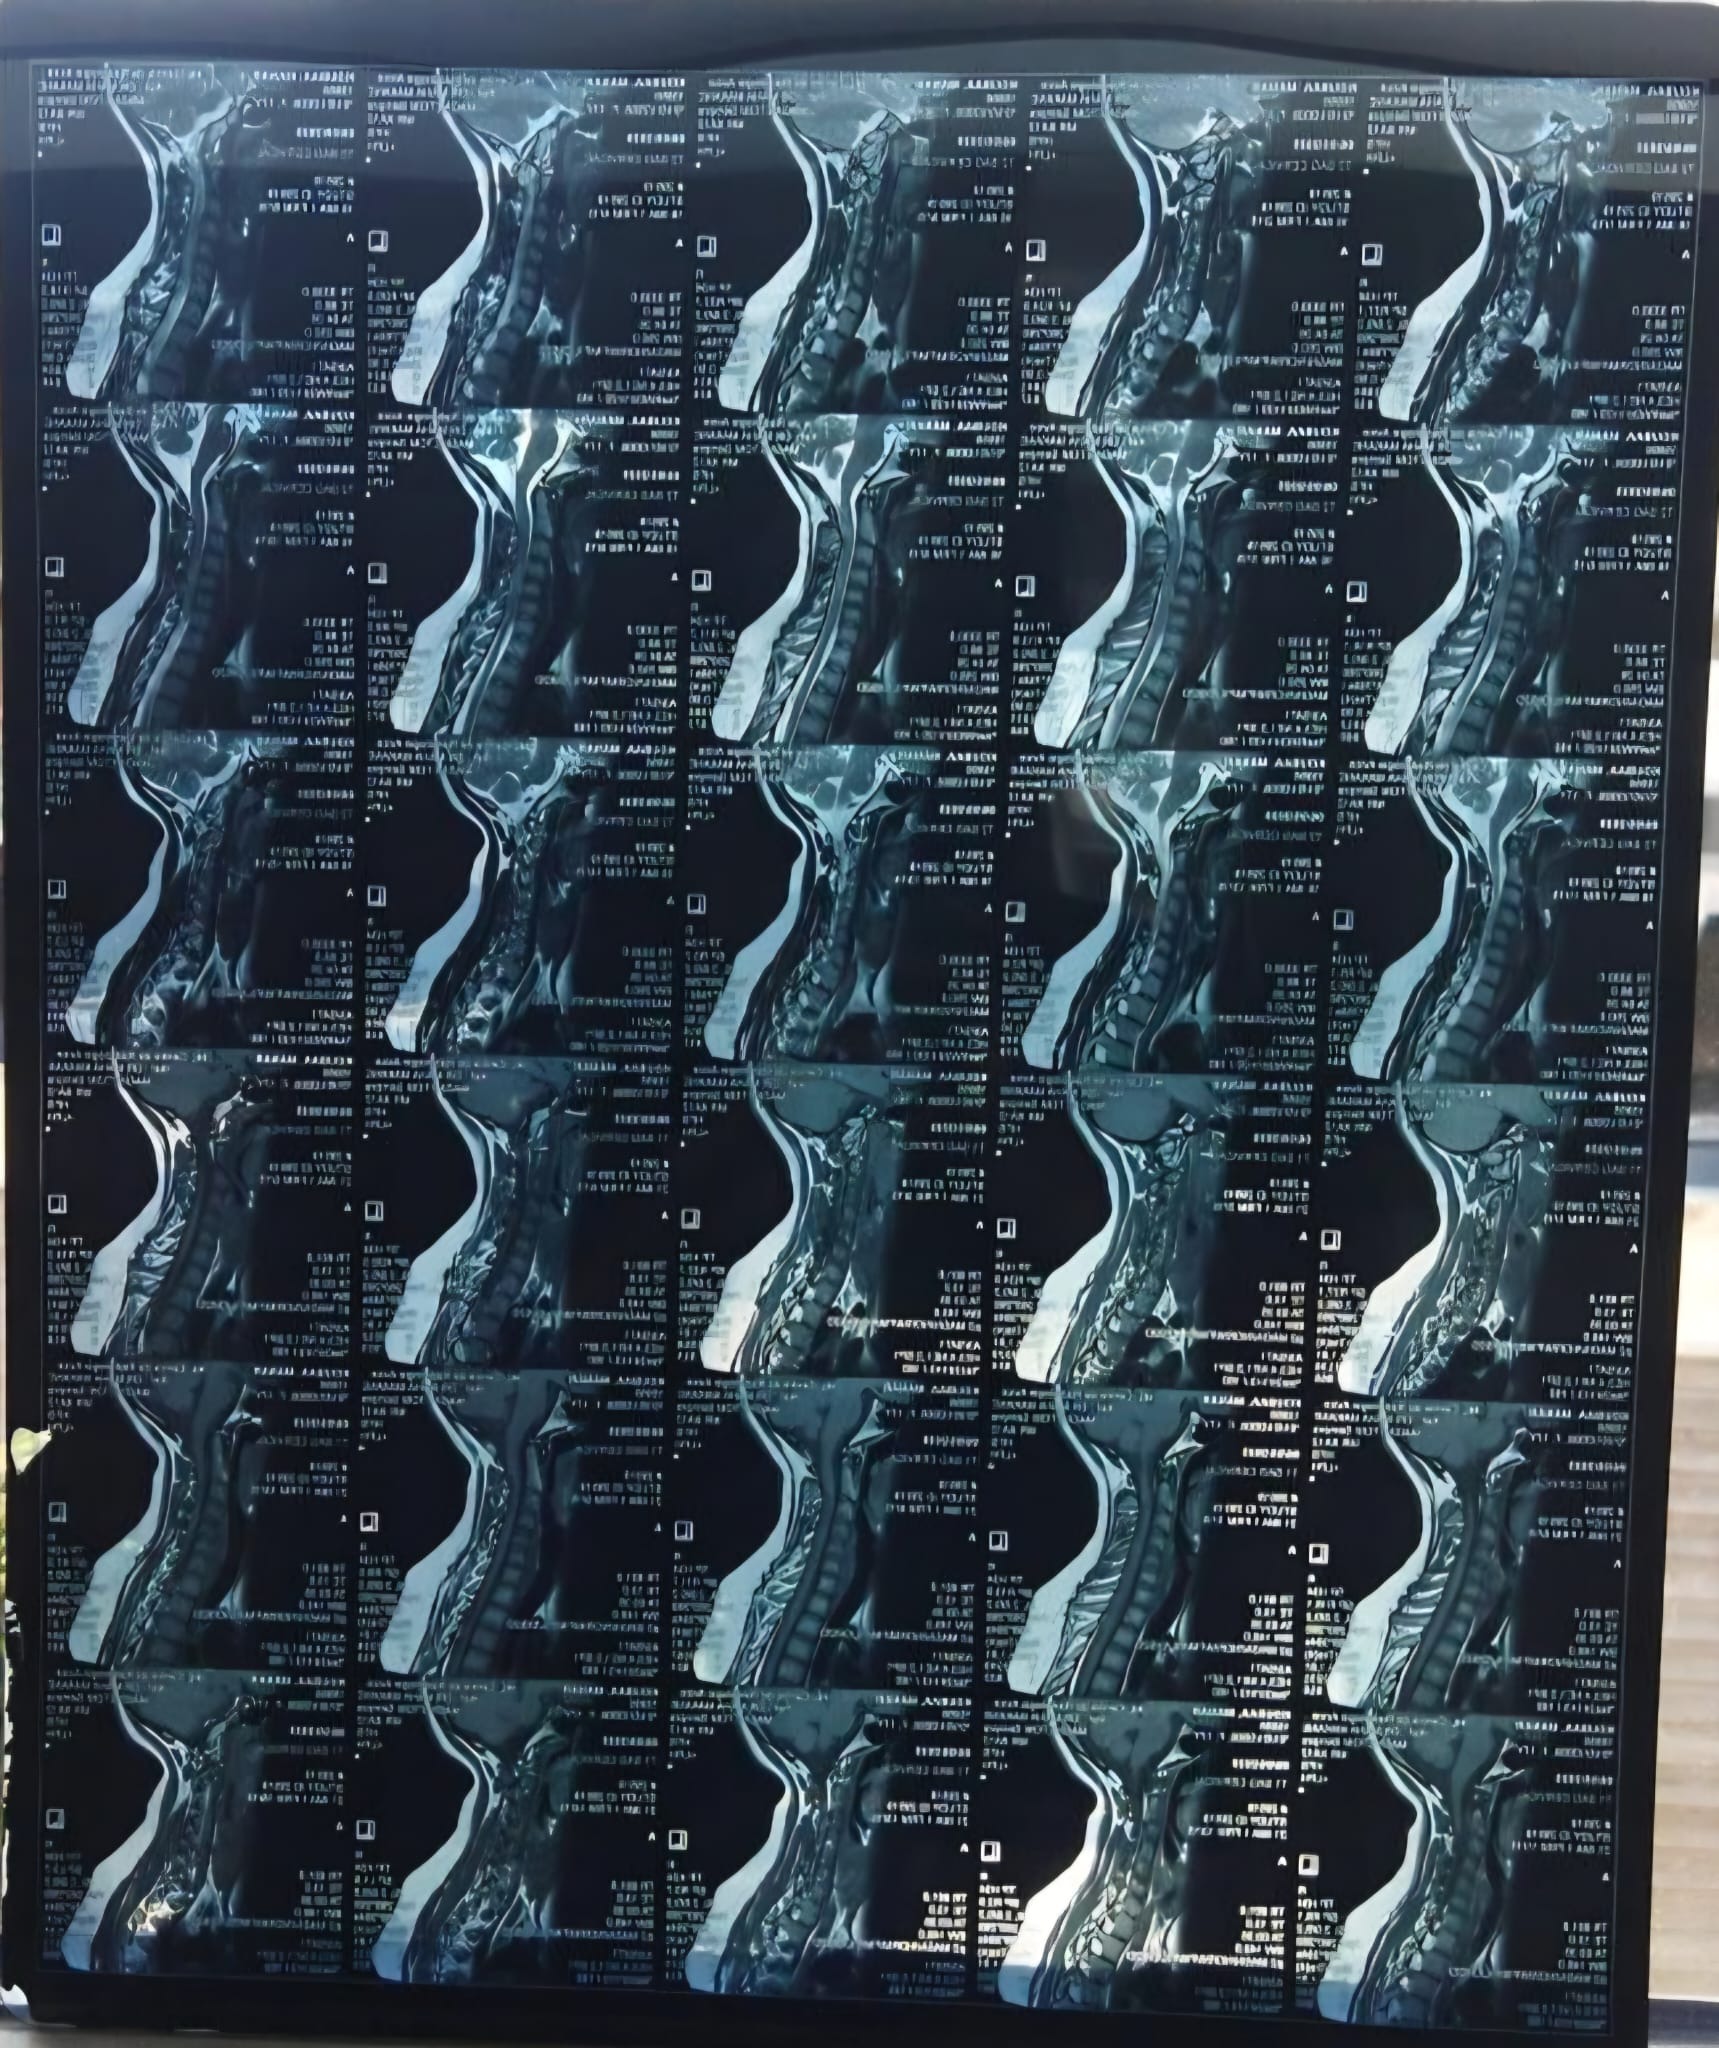

Ik ben Manar, ik ben 17 jaar oud. In mei 2025 heb ik de diagnose MS gekregen. Ik had veel last van duizeligheid, vermoeidheid en uiteindelijk dubbelzien. Uit verschillende onderzoeken is de diagnose MS vastgesteld. Iedere maand krijg ik via een infuus in het ziekenhuis medicatie toegediend, dit zorgt ervoor dat de ziekte geremd wordt. Helaas merk ik toch nog veel lichamelijke klachten waar ik dagelijks mee te maken heb. Dit beinvloed mijn dagelijks leven en het voortzetten van mijn studie. Al hamdoulilah 3la kouli hal.

Om te voorkomen dat mijn lichamelijke gezondheid niet verder achteruit gaat wil ik een stamcelbehandeling ondergaan in het buitenland. Een HSCT-behandeling, een intensieve behandeling waarbij het immuunsysteem wordt gereset. Deze behandeling kan de ziekte niet genezen, maar wel stopzetten en verdere verergering voorkomen. Deze behandeling kost € 65.000. Ik vertrouw er op met behulp van Allah en onze geweldige ummah dit bedrag te kunnen verzamelen, in sha allah.